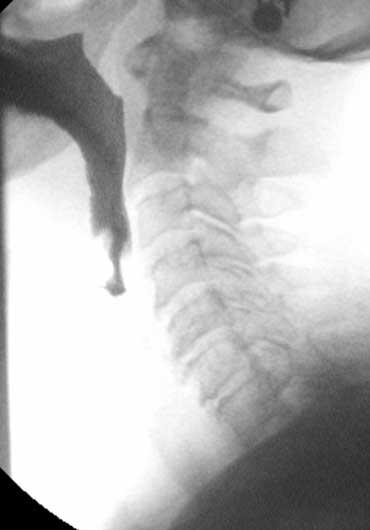

Thăm khám thực quản

Luôn theo dõi quá trình di chuyển của barium qua thực quản cho đến khi vào dạ dày.

Các rối loạn tại vùng nối thực quản-dạ dày thường được bệnh nhân cảm nhận như một vấn đề ở vùng họng.

Lý giải cho điều này là ở những bệnh nhân có tắc nghẽn đoạn xa, trào ngược dạ dày-thực quản hoặc rối loạn vận động, cơ nhẫn hầu phải hoạt động rất mạnh để ngăn thức ăn trào ngược lại vào hầu họng — kèm theo nguy cơ hít sặc.

Trương lực cơ tăng cao này tạo cho bệnh nhân cảm giác có vật gì đó trong cổ họng.

Các hình ảnh là của một bệnh nhân có cảm giác vướng họng (globus sensation).

Nguyên nhân là do trào ngược nặng và tình trạng tăng trương lực cơ nhẫn hầu thứ phát.

Thoát vị cạnh thực quản lớn kèm trào ngược là nguyên nhân gây ra các triệu chứng.

Hình ảnh tối ưu của vùng nối dạ dày-thực quản khi khí trào ngược từ dạ dày vào thực quản đã được phủ thuốc cản quang ở bệnh nhân thoát vị hoành trượt.

Có thể đạt được hình ảnh xuất sắc của vùng nối dạ dày-thực quản bằng cách thực hiện các bước sau:

- Yêu cầu bệnh nhân uống viên sủi zoru-granules (hoặc coca cola) để tạo đầy hơi tối ưu trong dạ dày.

- Dặn bệnh nhân không ợ hơi, mà giữ hơi trong dạ dày cho đến thời điểm nuốt.

- Đặt bệnh nhân ở tư thế chếch trước-trái (left anterior oblique).

- Nâng mặt bàn lên 45 độ.

- Nuốt barium tỷ trọng cao để phủ thực quản tối ưu.

- Chụp hình ảnh khi khí trào ngược từ dạ dày vào thực quản đã được phủ barium.

Ánh sáng tốt nhất đạt được khi phần trước của cột sống cổ nằm ở trung tâm hình ảnh.

Không đặt bolus thuốc cản quang vào trung tâm hình ảnh, vì trên video sẽ xuất hiện sự chuyển đổi liên tục giữa các hình ảnh quá tối và quá sáng.